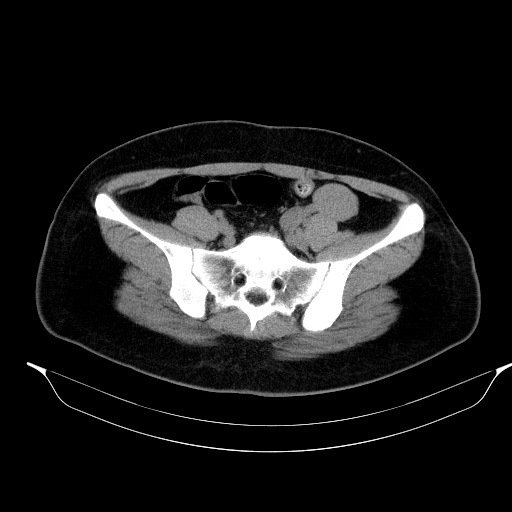

조영증강 후 영상에서 각 부위에서 뚜렷한 조영증강은 보이지 않았습니다.

초음파영상에서 보였던 낭성병변은 CT에서는 하행결장과 뚜렷하게 떨어져 있었기에 duplication cyst는 배제할 수 있으며, lymphangitic cyst의 가능성도 떨어져 보입니다. 해당 병변은 Lt. adnexal region에 있는 병변으로 생각됩니다.

조영증강이 되지 않고, 초음파에서 무에코음영을 보인 부분은 단순낭종으로 생각할 수 있습니다. 초음파영상에서 약간의 에코음영이 보였던 부위는 조영증강이 되지 않은 대신 균일한 연부조직음영을 보여 낭종 내에 출혈 가능성을 배제하기 어려웠습니다.